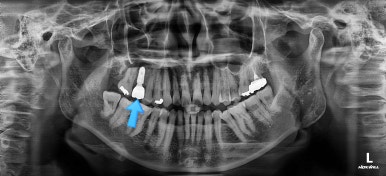

어금니를 뒤로 밀어주기 위해서 미니스크류와 브라켓, 철사를 이용해줘요.

중간중간 장치 디자인이나 미니스크류의 위치를 바꿔주기도 하고요.

점점 자리가 확보되어가는게 보이시죠?

적절한 공간이 확보되었다고 판단되면 임플란트를 식립합니다.

임플란트가 뼈에 단단히 붙을 몇 개월의 시간동안 부산교정치료를 좀 더 마무리 해주고요.

임플란트 머리 부분까지 완성이 되었어요.